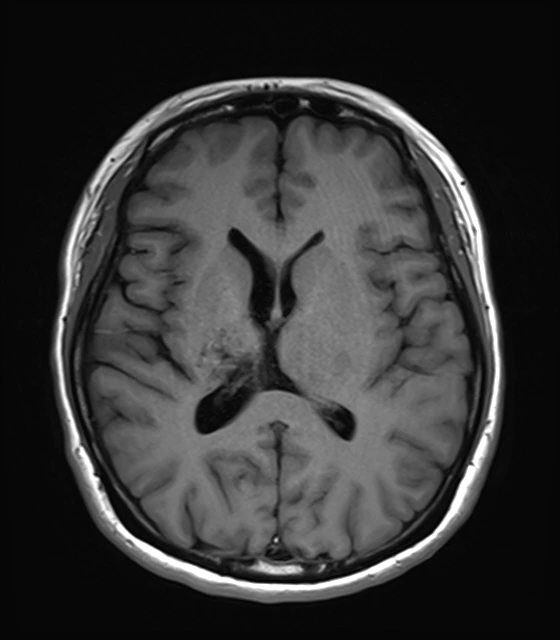

내가 정식으로 진단받은 병명은 ‘동정맥기형 파열에 의한 뇌내출혈’이다. 나는 뇌혈관이 터져버리는 출혈성 뇌출혈로 진단받았고, 출혈 부위는 대뇌, 그 중에서도 기저핵과 시상일부로 여러 부위에 걸친 대형의 기형혈관이 터지면서 뇌손상을 입었다. 고혈압이나 당뇨 등 기저질환을 앓고 있지도 않았는데 갑작스런 뇌출혈로 고생하는 젊은 뇌졸중 환자들은 대부분 이 동정맥기형 때문인 것 같았다.

동맥에서 모세혈관을 거쳐 정맥으로 흐르는 것이 정상인 혈류가 모세혈관을 거치지 않고 동맥에서 정맥으로 직접 흘러서 생기는 비정상적인 혈관의 집합체를 말한다. 중간에 이상 혈관 덩어리인 혈관괴(血管塊)가 생긴다. 주로 대뇌의 표면부에서 안쪽으로 걸쳐서 생기지만 깊은 부위에서 생길 수도 있다. 혈관괴는 성장함에 따라서 조금씩 커지며, 동정맥기형 내의 혈류 속도도 점점 빨라진다. 남자가 여자보다 약간 더 많이 발생하며, 유병률은 0.14%가 조금 넘는 것으로 알려져 있다. 발병연령은 약 33세 전후로 이 가운데 64%가 40세 이전에 진단을 받는 것으로 알려져 있다. 다음의 4가지 신경학적인 증세가 나타난다. ① 뇌출혈 : 동정맥기형이 파열되어 나타나는 증세로 30세 이전에 일어나는 뇌출혈의 가장 많은 원인을 차지한다. 갑작스러운 구토, 두통, 반신마비, 의식변화 등이 생긴다. 출혈이 일어날 때마다 신경학적인 결손을 나타내는 경우가 30∼50%, 사망률이 10%인 것으로 알려져 있다. ② 전간 : 뇌동정맥기형이 주위의 조직을 자극하여 일어난다. 나이가 어릴수록 전간이 일어나는 경우가 많다. 많이 발생하는 연령은 약 25세로 알려져 있고, 뇌동정맥기형의 크기가 클수록 전간에 의한 증세가 많이 나타난다. ③ 편두통 : 뇌동정맥기형 자체가 주위 신경조직을 눌러서 생긴다. 한쪽에 심한 두통이 나타나는데 일반적인 편두통과의 구별이 어렵기 때문에 정밀검사가 필요하다. ④ 뇌빈혈 : 기형이 있는 주위의 뇌에 충분한 혈액 공급이 안되어 생기는 것으로 반신마비, 언어장애, 감각이상 등의 증세가 나타난다. 치료방법은 다음과 같다. ① 수술 : 개두술로 뇌동정맥기형을 제거하는 것이다. ② 방사선수술 : 기형핵이 약 3㎝ 이하인 뇌동정맥기형인 경우에 시행하는 것으로 기형핵에만 방사선을 국소적으로 조사하는 방법이다. ③ 혈관내색전술 : 혈관 안으로 도자를 넣어서 색전물질을 기형핵에 주입하여 기형혈관을 막는 방법이다. [네이버 지식백과] 뇌동정맥기형 [cerebral arteriovenous malformation, 腦動靜脈畸形] (두산백과 두피디아, 두산백과)

뇌CT,MRI,혈관MRI(왼쪽위부터시계방향으로)-아래사진 좌측윗부분의 혈관뭉치가 기형혈관)